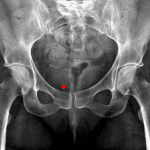

- Acute minimally displaced fracture of the right pubic body

- Mild degenerative changes of the hips, sacroiliac joints, and pubic symphysis

- Partially imaged mild degenerative changes of the lower lumbar spine

- Right os acetabuli

- Bilateral coxa profunda

- Pubic body fracture

Acute minimally displaced fracture of the right pubic body.

No symphyseal widening or joint malalignment.

Mild degenerative changes of the hips, sacroiliac joints, and pubic symphysis.

Partially imaged mild degenerative changes of the lower lumbar spine.

Right os acetabuli and bilateral coxa profunda, which although possibly incidental can be seen with pincer-type femoro-acetabular impingement.